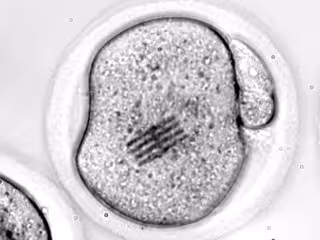

Archivo - Embrión con un chip en su citoplasma

Archivo - Embrión con un chip en su citoplasma - REMITIDA UGR - Archivo